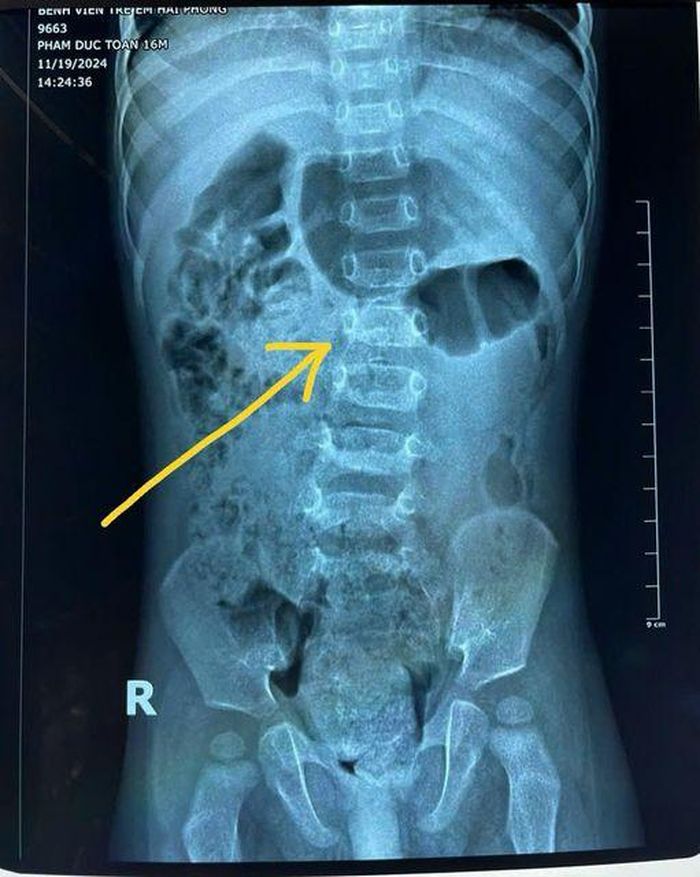

Old  Default Bé 16 tháng tuổi đã cong vẹo cột sống vì cha mẹ cho tập ngồi từ 7 tháng

Khoa Y học cổ truyền - Phục hồi chức năng, Bệnh viện Trẻ em Hải Phòng liên tiếp tiếp nhận bệnh nhi bị gù vẹo cột sống thắt lưng, trong đó nguyên nhân chủ yếu do cha mẹ ép con tập ngồi quá sớm.

Thông tin từ Bệnh viện Trẻ em Hải Phòng cho biết, thời gian gần đây, Khoa Y học cổ truyền - Phục hồi chức năng của đơn vị liên tiếp tiếp nhận bệnh nhi (đặc biệt trẻ 16 tháng tuổi) bị gù vẹo cột sống thắt lưng. Nguyên nhân chủ yếu bắt nguồn từ việc cha mẹ ép con tập ngồi quá sớm và kéo dài trong thời gian dài, khi cơ thể trẻ chưa đủ sức nâng đỡ cột sống.

Qua quá trình thăm khám, các bác sĩ bệnh viện Trẻ em Hải Phòng nhận thấy, nhiều trẻ bị chậm phát triển vận động. Trường hợp cụ thể điển hình là trẻ 5,5 tháng tuổi mới bắt đầu tập lẫy nhưng khả năng lẫy còn yếu. Đến 7 tháng tuổi, khi chưa tự ngồi được, cha mẹ đã đặt trẻ ngồi và giữ ở tư thế này trong thời gian dài.

Hình ảnh cột sống của trẻ bị cong vẹo do thói quen mắc phải của cha mẹ. Ảnh: BVCC

Điều đáng lưu ý là ở giai đoạn này, cơ cạnh cột sống thắt lưng của trẻ còn yếu, không đủ sức nâng đỡ cột sống một cách vững vàng. Trong một số trường hợp, trẻ còn bị giảm cơ lực toàn thân, đặc biệt là bên trái, kết hợp với tình trạng tăng trương lực cơ. Khi trẻ phải ngồi lâu trong tư thế không tự nhiên, cột sống bị áp lực lớn dẫn đến tình trạng cong vẹo nghiêm trọng.